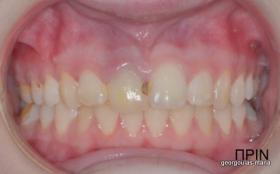

Η κοπέλα αυτή ήρθε στο ιατρείο με κάταγμα στον δεξιό άνω κεντρικό τομέα. Το δόντι είχε απονευρωθεί στο παρελθόν και είχε αποκατασταθεί με βιδωτό άξονα κ ανασύσταση με ρητίνη και το αισθητικό αποτέλεσμα ήταν φτωχό. Η ασθενής ήθελε να είναι καλυμμένη αισθητικά για όσο χρονικό διάστημα θα διαρκούσε η θεραπεία. Πραγματοποιήθηκε τομογραφία κωνικής δέσμης (CBCT) στην περιοχή και αποφασίστηκε να γίνει εξαγωγή του δοντιού, διατήρηση του όγκου του φατνίου και 3 μήνες μετά τοποθέτηση εμφυτεύματος με ταυτόχρονη χρήση μοσχευμάτων σκληρών κ μαλακών ιστών  για βέλτιστο αισθητικό αποτέλεσμα. Το εμφύτευμα αποκαταστάθηκε με υβριδικό κολόβωμα από διπυριτικό λίθιο και ολοκεραμική στεφάνη από διπυριτικό λίθιο (Emax). Καθ’ όλη τη διάρκεια της θεραπείας, η ασθενής ήταν καλυμμένη αισθητικά με γέφυρα Meryland  συγκολλημένη στα δύο διπλανά δόντια. Μετά την οστεοενσώματωση του εμφυτεύματος και πριν την τελική αποκατάσταση, τοποθετήθηκε στο εμφύτευμα προσωρινή εργασία με σκοπό τη βελτίωση των ούλων.